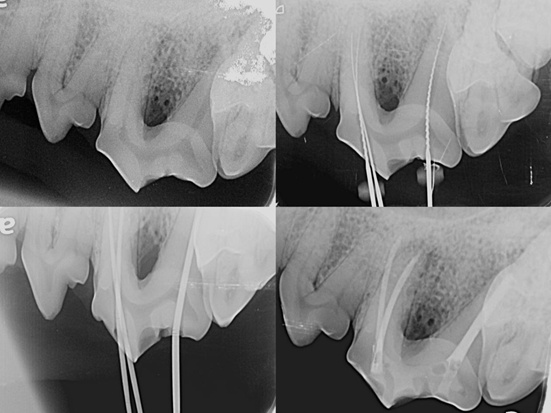

养宠家庭注意啦,毛孩子牙齿磕断可别当小事!暴露的牙髓腔容易滋生细菌,引发疼痛甚至全身感染。 近日,闵行柏萃动物医院接诊了一只牙齿复杂冠折的柯基,通过精准根管治疗保住了功能齿。今天就来科普宠物牙损伤的正确处理方式,帮大家避开养护误区。 当遇到因意外导致牙齿断裂的毛孩子,很多主人最初会认为“只是牙齿磕掉一块,不影响吃饭就行”。但其实暴露的牙髓腔就像一扇向细菌敞开的大门,引发的疼痛和感染风险,远超想象。今天故事的主角,是一只遭遇108号上颌第四前臼齿复杂冠折的柯基犬。 临床检查与诊断 口腔视诊可见口腔卫生状况良好,未见严重牙结石,存在牙菌斑。108号牙齿发生复杂齿折,颊侧釉质与本质碎片缺失,牙髓腔直接暴露于口腔环境。 随后医生为它进行了全身麻醉下的牙科X光片检查。X光影像显示:齿折线已延伸至髓腔,导致牙髓直接暴露。 幸运的是,因事发时间较短,牙根尖周区域未见明显低密度影,表明尚无根尖周炎性病变与牙槽骨吸收。 三个牙根(近中颊根、远中颊根、腭根)结构完整,未见根折迹象。 治疗决策:拔牙与根管治疗的权衡 牙髓暴露后,口腔内的复杂菌群会经由根管系统侵入根尖周组织,可能引发根尖周脓肿、根尖肉芽肿或囊肿,导致持续性疼痛。感染甚至可能通过血行播散,危及心、肾等远端器官。 面对此情况,我们有两种治疗方案:拔牙或根管治疗。 什么是根管治疗? 根管治疗,是针对牙髓发生不可逆性损伤(如暴露、感染或坏死)后,为保留牙齿本身而进行的精细治疗。其核心在于: 1.彻底清除根管内所有感染、坏死的牙髓组织。 2.对复杂的根管系统进行成形、冲洗和消毒。 3.使用生物相容性材料严密充填根管,隔绝再感染途径。 最终达到消除疼痛、清除感染源、保留牙齿自然结构与功能的目标。 为什么选择根管治疗? 功能保留:108号牙齿是犬只重要的功能齿,承担着主要的剪切与咀嚼力量。根管治疗能最大程度地保留其正常的生理功能,避免因拔牙导致的咀嚼方式改变、邻牙移位或对颌牙过度萌出等问题。 结构维持:牙根的存在对维持下颌骨与上颌骨的骨量至关重要。保留牙根可以防止该区域颌骨因失去功能性刺激而出现的废用性萎缩。 微创与美观:相较于拔除大型牙齿,根管治疗是微创且生物相容性更佳的选择,能完整保持牙列外观与口腔结构的完整性。 手术圆满成功。整个手术过程,医生凭借专业的诊疗判断和精细操作,一步步攻克复杂根管系统的清洁、成形与充填难题,最大程度降低了治疗对毛孩子的身体影响。术后一年复诊,X光片显示根尖周组织健康无异常,修复体完好,患牙功能正常。此类复杂冠折的根管治疗,要求医生具备完备的牙科知识、精湛的显微操作技术以及丰富的临床经验。